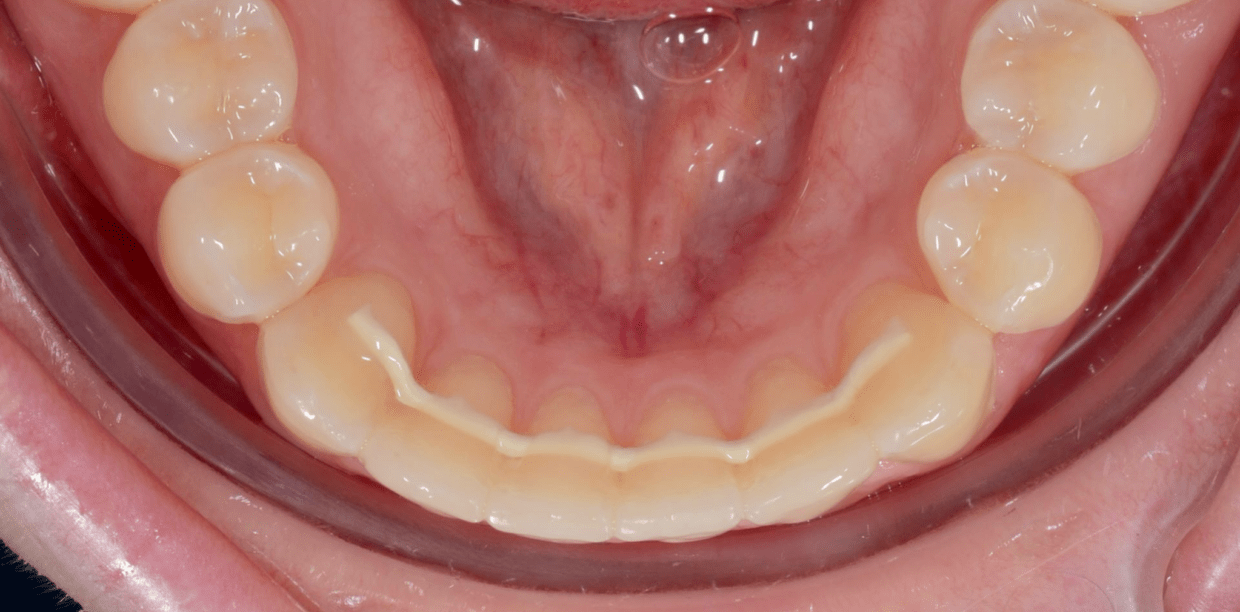

Simple - A2

Simple - A2

Simple - A2

Simple - A2

Simple - A2

Simple - A2

Simple - A2

Simple - A2